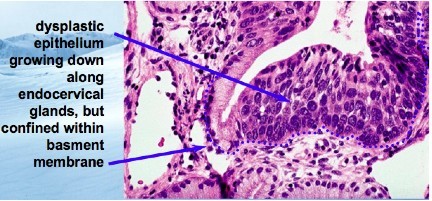

What is the concern regarding the histologic specimen below?

Microinvasive carcinoma: small nests of cells just barely penetrating epithelial basement membrane. Can invade vessels or metastasize to lymph nodes.